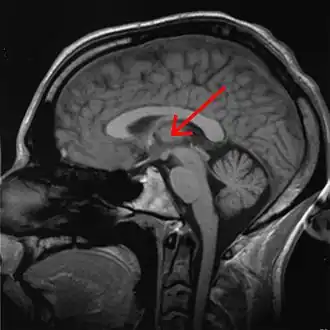

Ядра таламуса

![]() Список ядер таламуса: MNG = Срединная группа ядер AN = Передние ядра таламуса MD = Медиальное дорсальное ядро VNG = Вентральная группа ядер VA = Вентральное переднее ядро VL = Вентральное латеральное ядро VPL = Вентральное постеролатеральное ядро VPM = Вентральное постеромедиальное ядро LNG = Латеральная группа ядер PUL = Ядра подушки MTh = Метаталамус LG = Латеральное коленчатое тело MG = Медиальное коленчатое тело | |

Таламус состоит из нескольких отдельных областей серого вещества. Эти области представляют собой группы таламических ядер, разделённых областями белого вещества. Белое вещество, разделяющее и облегающее отдельные таламические ядра и группы ядер, представляет собой пучки миелинизированных нервных волокон. Кроме того, в таламусе выделяют также особые группы нейронов, отличающихся по своему гистологическому строению и биохимическому составу от остальной части таламуса, такие, как перивентрикулярное ядро, внутрипластинчатые ядра, так называемое ограниченное ядро и другие[3]. Эти отличающиеся по своей гистологической структуре и биохимическому составу от остальных ядер таламуса особенные ядра обычно группируют в так называемый аллоталамус, в противоположность «типичным» таламическим ядрам, которые группируют в так называемый изоталамус[7].

Ядра таламуса на основании особенностей их анатомо-гистологической структуры и цитоархитектоники можно подразделить на шесть групп: передние, медиальные, боковые, ретикулярные, внутрипластинчатые ядра и ядра средней линии. Тонкий Y-образный слой миелинизированных нервных волокон, так называемая внутренняя мозговая пластинка, разграничивает между собой переднюю, срединную и боковую группы таламических ядер. У человека передняя и срединная группы таламических ядер содержат всего по одному большому ядру, называемому соответственно передним дорсальным и медиальным дорсальным ядрами таламуса. Между тем боковая группа ядер таламуса человека подразделяется на дорсальный и вентральный уровни. Дорсальный уровень боковых ядер таламуса человека состоит из бокового дорсального, бокового заднего ядер и ядер подушки таламуса. Вентральный уровень боковых ядер таламуса человека, в свою очередь, состоит из вентрального переднего, вентрального бокового, вентрального задне-бокового и вентральных задних медиальных ядер[8].

Боковая группа ядер таламуса покрыта другим тонким слоем миелинизированных нервных волокон — так называемой наружной мозговой пластинкой. Между этим пучком нервных волокон и внутренней капсулой находится тонкий слой ГАМКергических нейронов, образующих ретикулярное ядро. Группа внутрипластинчатых ядер таламуса, среди которых самым крупным является так называемое центральное срединное ядро таламуса, как следует из её названия, располагается внутри Y-образной внутренней мозговой пластинки[8].